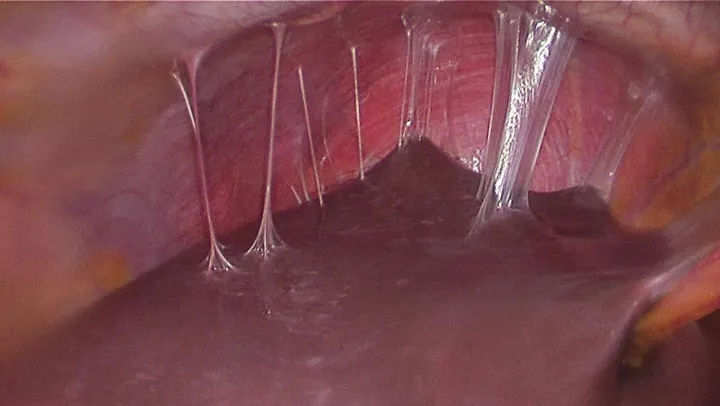

Fıtık onarımının dünya çapında en yaygın cerrahi prosedürlerin başında geldiğine işaret eden Prof. Dr. Esra Karaca, her yıl yaklaşık 20 milyon hastanın fıtık gelişimine bağlı olarak ameliyat edildiğini açıkladı. Karın duvarında oluşan defektin, mesh adı verilen bir tıbbi tekstil materyali implante edilerek onarılmasının da bu alanda yapılan en yaygın cerrahi müdahalelerden birisi olduğunu söyleyen Prof. Dr. Esra Karaca, 'Bununla beraber, kullanılan meshler ciddi adezyonlara neden olmaktadır. Daha önce fıtık ameliyatı olmuş hastaların yüzde 90'ından fazlasının ameliyat sonrası adezyon semptomları gösterdiği tespit edilmiştir. Adezyonlar ise kronik karın ağrılarına ve iç organlarda ölümcül tıkanıklıklara yol açabilmektedir. Yeni ürünler denenmesine rağmen, post-operatif adezyon henüz başarıyla önlenememiştir. BUÜ Tıp Fakültesi Hastanesi'nden Türkiye ile ilgili bir projeksiyon yapılarak, ülkemizde bir yılda kullanılan fıtık mesh sayısının 100 bin civarında olduğu sonucuna varılmıştır. Bu nedenle; proje çerçevesinde geliştirilecek başarılı bir kompozit meshin, yurt dışından mesh ithalatını önemli oranda azaltacağı öngörülmektedir' açıklamasında bulundu.

Karaca ayrıca projede, karın fıtıklarının onarımında kullanılmak üzere çörek otu yağı içeren anti-adezyon özellikli nanolifli yüzey ile takviyelendirilmiş PP örme mesh yapıların geliştirilmesi ve kompozit meshlerin fıtık onarımı ve adezyon önleme performansının in vitro ve in vivo çalışmalarıyla değerlendirilmesini hedeflediklerini de sözlerine ekledi.